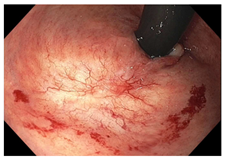

| Endoscopy | Flat white scar Telangiectasia Absence of ulcers and mucosal nodularity | Small mucosal nodules/minor mucosal irregularities Superficial ulceration Mild, persistent erythema of the scar | Visible tumor |

| Superficial ulceration | ![]() | ![]() | ![]() |

| Persisting erythema of scar | ![]() | ![]() | ![]() |